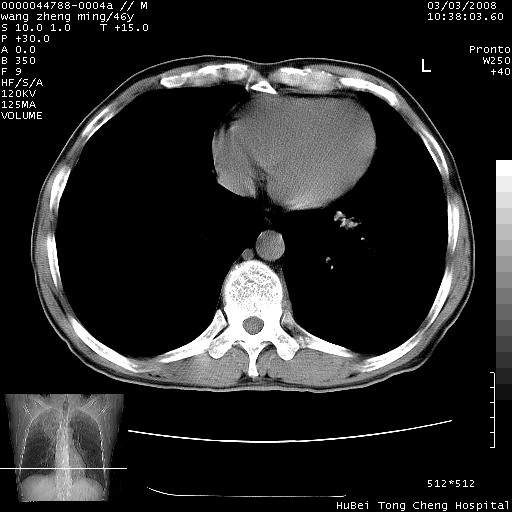

以下是引用卜一在2008-3-22 1:37:00的发言:[br]右肺实质性肿块,边缘不整,明显见毛刺征 分叶征及胸膜凹陷征,右上叶支气管明显变窄,远端散在的片状 斑片状实变影。另:左肺门较大肿块,支气管受累 变窄,远侧见阻塞性肺炎。纵隔内见肿大淋巴结。多考虑:右肺周围性肺癌伴左肺门 纵隔淋巴结转移!